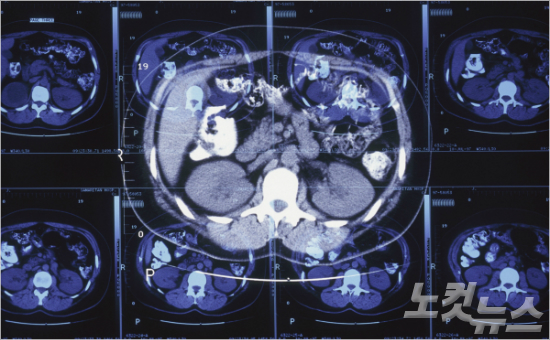

(사진=이미지비트)